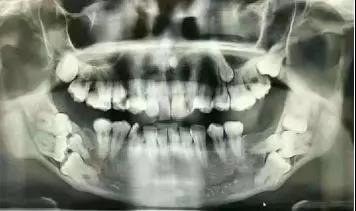

事实上,牙片是牙医的第三双眼睛。一直以为自己就长了三颗智齿呢,直到左侧6号牙坏了,拍了个牙片才知道,原来第四颗智齿长不出来了,但它一直都在。

近中阻生智齿,也就是图中1、2两颗横着向牙列方向长的智齿,非常容易将邻近的牙“顶坏”,所以不得不将这两颗牙拔掉。像智齿这样的下颌槽牙的牙根离面部神经非常近,一不小心就可能伤到神经,导致面部没有知觉。而牙片可以清晰地看到牙根与神经的距离,确定拔牙是不是有风险,这也是为什么拔牙都要拍牙片的原因。这口牙只能用“出车祸”来形容了。本以为下颌大牙先天性缺失,不曾想是牙胚的生长方向错了,大牙长不出来。

以上仅仅是列举了茫茫牙片中几个微不足道的例子,但足以说明牙片的重要性。隐藏在牙龈下方的疾病,医生光凭肉眼是无法看到的,不对症,如何用药?即使是拔除一颗坏牙,也要确定会不会伤害到下颌面部神经。由此可见,牙片是牙医的“第三只眼睛”,能看见肉眼看不到的病灶。